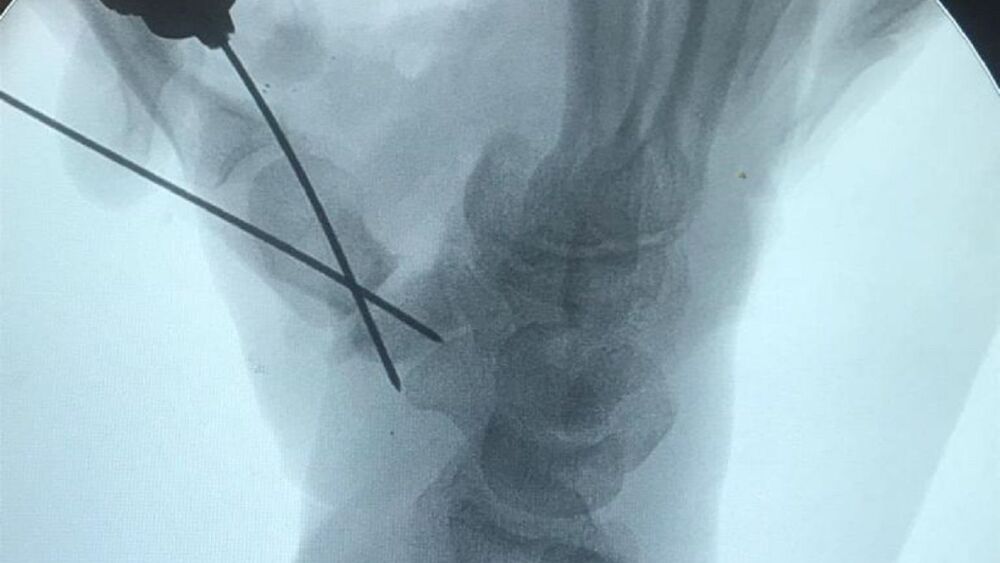

Profesionales del Hospital Central de IPS realizaron con éxito una compleja cirugía de pulgarización de un dedo índice en la mano derecha de un paciente, lo que permitirá que el mismo pueda recuperar la funcionalidad de su miembro.

El paciente de 57 años, oriundo de San Juan Bautista, Misiones, fue atendido por profesionales de Ortopedia y Traumatología del Instituto de Previsión Social (IPS), tras sufrir una amputación del pulgar de su mano derecha.

Posteriormente, el mismo fue sometido a una compleja cirugía liderada por los cirujanos Rodrigo Romberg y Alcides García, quienes realizaron con éxito la trasferencia del dedo índice con todo lo que implica, arteria, nervios al lugar del pulgar.

Con la intervención, el objetivo es que el paciente recupere la funcionalidad de pinza en la mano derecha y así volver a realizar sus actividades diarias.

Según informó la previsional, el paciente sigue internado y evolucionando favorablemente en el servicio de Traumatología del Hospital Central del IPS.